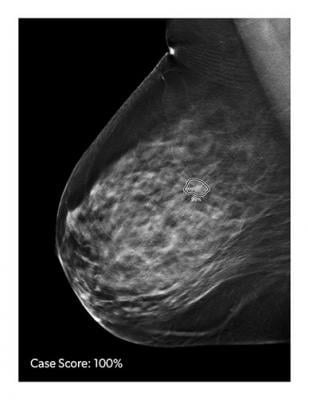

ProFound AI is a high-performance, deep-learning, cancer detection and workflow solution for DBT, delivering improvement of cancer detection rates by an average of 8 percent and decreasing unnecessary patient recall rates by an average of 7 percent. The new technology is trained to detect malignant soft-tissue densities and calcifications. It also provides radiologists with scoring information representing the likelihood that a detection or case is malignant based on the large dataset of clinical images used to train the algorithm.